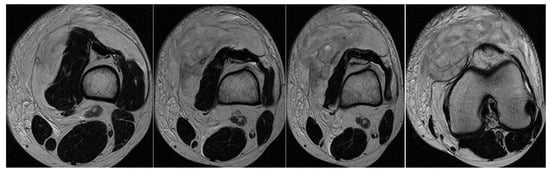

3.3. Case 3: Adductor Complex Strain

In the third case, a left winger reported experiencing sharp pain in the inner left thigh, which severely impaired both active and passive movements during sprints. The left winger, aged 32, has 14 years of experience as a first-league professional in Romania and is a national team member from an urban area, standing 189 cm tall and weighing 90 kg. MRI confirmed the diagnosis of tears and disinsertion of the short adductor tendon and I- and II-degree tears of the obturator externus, pectineus, and adductor longus muscles. STIR sequences show the disinsertion of the short adductor tendon with a gap between the tendon and pubis, with the presence of significant hyperintense alterations, which were also present in the obturator externus, pectineus, and adductor brevis muscles, representing various degrees of fiber tears associated with blood clots (Figure 8).

(a) Thigh MRI: coronal stir acquisition, (b) thigh MRI: coronal stir acquisition, (c) thigh MRI: axial stir acquisition.

As the reinsertion of the adductor brevis muscle involved an unacceptable period of incapacitation, the adductor magnus, the strongest muscle in the adductor group, being unimpaired, conservative treatment was applied, the player started a physical therapy program focusing on healing first- and second-degree muscle damage, respectively, the hypertonicity and hypertrophy of the other adductor muscles, mainly of the adductor magnus, the strongest muscle in the group. He returned to play after 6 weeks.